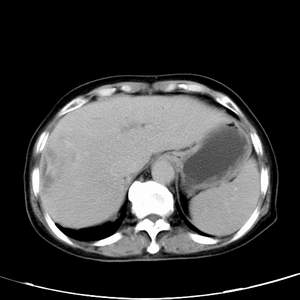

患者,女性,77岁,右上腹胀痛月余。afp正常。ca125升高。即往无肝炎病史。

肝右叶病灶是胆管细胞癌吗?门静脉右支癌栓形成?右侧肾上腺有问题吗?

最后5幅图片是延时7分钟的。门静脉右前支内有充缺吗?如有,肝血管瘤不好解释。

渐进性强化,中间见沙砾样钙化,首先考虑血管瘤

病灶渐进性向心性强化,延时病灶中心见条片状高密度影,局部见肝包膜回缩征,结合病人无肝炎病史,考虑肝右叶胆管细胞癌,门脉右支癌栓形成。